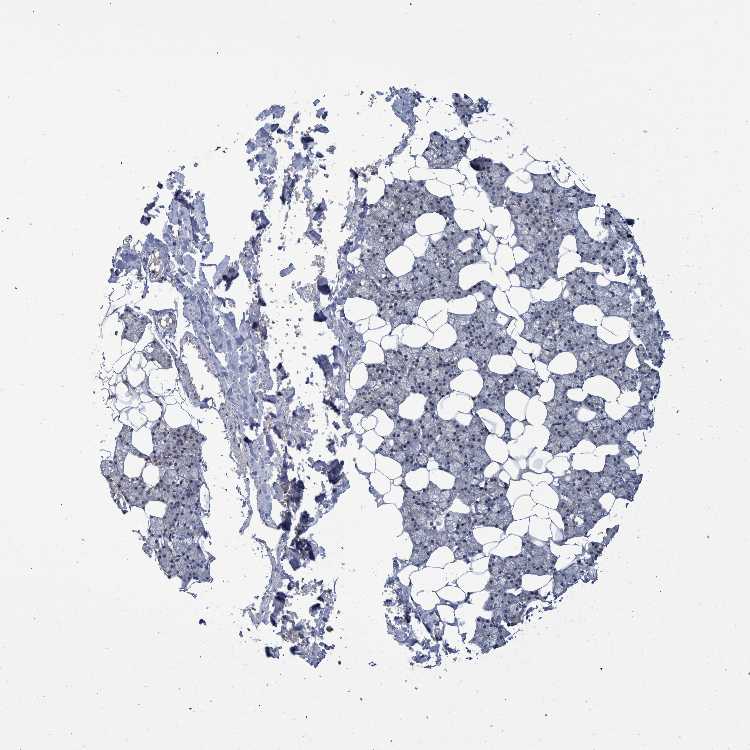

SALIVARY GLAND - Antibody stainingi

Antibody staining in the annotated cell types in the current human tissue is reported as not detected, low, medium, or high, based on conventional immunohistochemistry profiling in selected tissues. This score is based on the combination of the staining intensity and fraction of stained cells.

Each image is clickable and will lead to virtual microscopy that enables deeper exploration of all samples and also displays staining intensity scores, fraction scores and subcellular localization as well as patient and tissue information for each sample.

Antibody HPA023033Antibody HPA023034

Glandular cells LowMedium